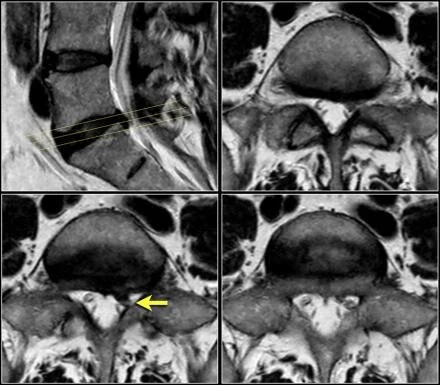

MRI - Nerve Pinching